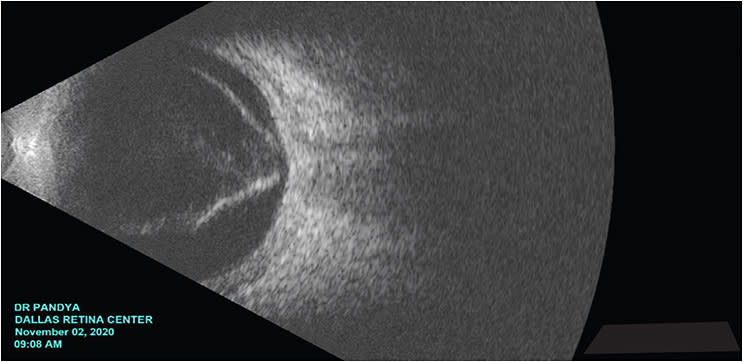

In traumatic retinal detachments, it is important to assess pupillary dilation, baseline inflammation, and lens status. Traumatic events can lead to sequelae of intraocular inflammation (corneal edema, posterior synechiae) and lens opacification. These changes can limit direct visualization of the posterior segment.

It is also important to appreciate the emotional aspects of vision loss. Their funnel retinal detachments may have an unfavorable configuration, and may be inoperable. Surgical intervention has the risk of leading to worsening vision. Always consider the psychological aspects of going from light perception (LP) to no light perception (NLP). NRP